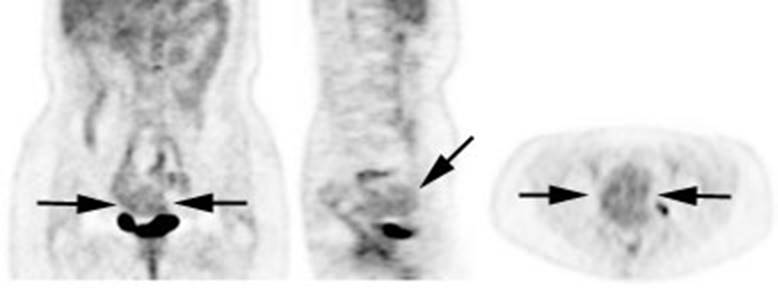

uterine uptake is common (black arrows).

Figure 25 - Normal

testicular activity: Mild

symmetric testicular uptake can be seen (black arrows)

Figure 26 - Normal

vascular activity: Faint

activity can be seen in the descending thoracic aorta (black arrows)

Figure 27 - Normal

breast activity: Faint

activity can normally be seen in the breasts (black arrows)